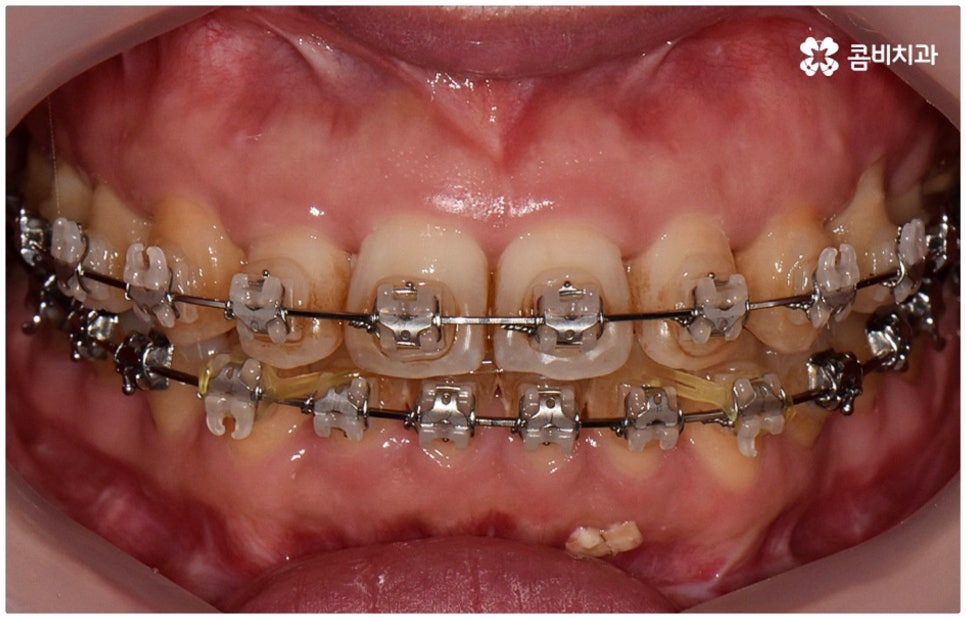

출처 아카이브 열기위아래 치열이 제대로 맞물리지 않으면 음식물을 씹을 때 어려움을 느끼거나 발음상 문제가 생길 수 있습니다. 이것을 부정교합이라고 하며, 그 종류는 상악과 하악의 골격적인 전후방 관계를 기준으로 1급, 2급, 3급으로 나눌 수 있어요. 위아래 어금니는 잘 맞물리는데 치열이 조금씩 삐뚤어져 있거나 치아 사이가 벌어져 있는 등 살짝씩 어긋난 부정교합은 1급, 위 어금니가 더 앞으로 나가있는 부정교합은 2급 (ex. 돌출입), 그리고 아래 어금니가 더 앞으로 나가있는 부정교합은 3급 (ex. 주걱턱) 으로 분류하게 되는데 이 중 오늘 살펴보려고 하는 것은 부정교합 3급에 해당하는 반대교합에 대한 거예요.

정상적인 교합은 윗 앞니가 아래 앞니를 살짝 덮는 정도로 윗니가 조금 더 앞으로 나와 있으면서 위아래 치아가 어금니까지 잘 맞물리는 것을 말하는데 반대교합은 위아래 앞니가 거꾸로 물리는 증상을 보이기 때문에 저작 활동 및 발음 조성이 원활하지 않게 되며 반대교합교정 등 적절한 치료를 받지 않고 방치할 경우 점점 더 주걱턱이 강화되는 쪽으로 뼈가 성장할 수 있어 될 수 있는 대로 빠른 시일 내에 원인을 분명하게 알아보고 그에 맞는 치료를 받는 것이 중요하다고 할 수 있어요.

관련 기술이 많이 발달하면서 교정 치료에 나이가 크게 중요하지 않게 된 것은 사실이지만 골격적인 원인을 가진 반대교합의 경우 말씀드린 것처럼 일상 생활을 하는데 크게 불편함을 초래할 수 있을 뿐 아니라 성장하면서 부정교합이 더욱 악화되는 쪽으로 상하악 발달이 불균형적으로 이루어질 수 있기 때문에 다른 부정교합에 비해 조금 더 빠른 시기에 진단과 치료를 진행할 필요가 있어요. 만약 성장기가 지나 정도가 심해지는 쪽으로 뼈가 굳어지게 된다면 교정 만으로 치료가 어렵고 양악 수술 등 외과적인 방법을 통해 치료를 받아야 하는 상황이 생길 수 있으므로 치료 시기를 놓치지 말고 원인을 정확하게 파악하고 그에 맞는 치료를 받는 것이 중요하다고 할 수 있습니다.

골격적인 원인으로 인한 것이라면 반대교합교정 치료를 할 때 위턱의 성장을 유도하고 상대적으로 아래턱 성장을 저지하는 방향으로 상악과 하악의 위치 관계를 개선하는 방법을 사용하게 되며 환자분들의 상황에 따라 악궁확장장치 또는 페이스마스크 등의 장치를 이용하게 되는데, 이렇게 골격적인 부분에 크게 영향을 받은 경우 재발의 가능성 역시 높기 때문에 어릴 때 교정 치료를 시작하여 치열이 고르게 돌아왔다고 해도 성장이 완료되는 시기까지 꾸준하게 관리를 해 줄 필요가 있어요.

교정 치료가 생물학적 반응을 이용하는 것이다 보니 성장기에 진행하면 치아 이동 및 회복 속도 등에 장점이 있는 것은 분명하지만 그렇다고 해서 성인 이후 중장년 분들이 교정 치료를 받을 수 없는 것은 아니며 이미 많은 분들이 도움을 받고 계신 만큼 이에 대해서 한 번 고려해 보시면 좋을 거예요. 혹시 성장기 이후로는 양악 수술 등으로만 치료가 가능한 것이 아닐까 생각하셔서 부담스럽게 느끼셨던 분들이라면 지레 겁을 먹고 불편함을 그대로 방치하시기 보다는 검진 및 상담을 통해 적극적으로 이를 해결해 보시길 권유드리고 있어요.

물론 원인과 정도에 따라 외과적인 방법이 필요하신 분들도 있을 수 있지만 교정을 통해 얼마든지 치료가 가능한 경우도 있으며 앞서 말씀드렸던 것처럼 발전된 교정 기술 및 특수 미니스크류 등의 장치 개발을 통해 턱의 방향을 조금씩 회전시켜 원거리 치아 이동을 유발하는 것이 가능해졌기 때문에 예전에는 한계가 있었던 부정교합 케이스도 개선될 여지가 늘어나고 있습니다. 꼼꼼하게 검진을 받으시고 자신의 상황에 맞는 교정 치료를 무리하지 않게 진행하신 후 철저하게 사후 관리를 해주시면 보다 오랜 기간 동안 건강하게 고른 치열을 유지하면서 생활하실 수 있을 거예요.